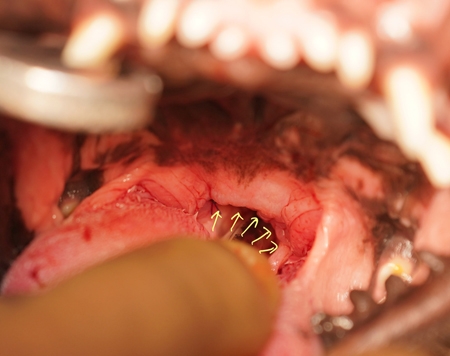

短頭種気道症候群 軟口蓋過長症 症例報告(高橋雅弘) 福岡県 春日市の犬猫病院 高橋ペットクリニック 外科ケースより 前々回の続きです。 短頭種気道症候群のつづきです。 メインである軟口蓋過長症は軟口蓋の切除を実施します。 長い軟口蓋を牽引しています! 切除ラインで切除して、解ける糸(吸収糸)で縫合します。 縫合後の所見です。 のどぼとけにかからない程度の長さになっています!! « 前の記事へ カテゴリ一覧ページに戻る 次の記事へ »